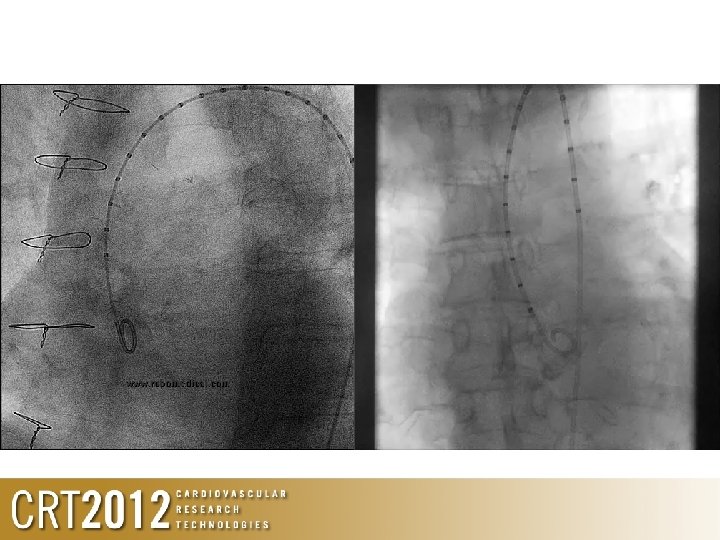

The Aortic Working View • Important for initial pre-assessment measurements • Essential to ensure implantation proceeds correctly • Should be obtained during diagnostic workup • Should be reaffirmed prior to crossing the aortic valve during TAVI procedure

Essentials of Aortic Angiography • Use imager angles that are ergonomic • Don’t ignore the anaesthetist • That does not require too much movement between RAO and implant view • Access to patient is still possible • Use graduated pigtail • Helps with spacial orientation and depth • Helps with post implant analysis • Use contrast volume and pressure that will delineate all 3 sinuses • Typically, 10 -15 mls at 900 Psi

‘Rules’ of using angiography for TAVR • Align the 3 sinuses in 1 plane – Convert 3 D anatomy to 2 D • Position the pigtail deep into the base of the non-coronary sinus – Helps with implantation • Adequate volume of contrast, under adequate pressure

Be prepared to make subtle changes to fluoro angle to ‘align’ valve to anulus 3 D Start at LAO 5 -10 2 D End at LAO 15, CAU 10